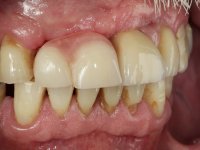

6 meses após a colocação da ponte, o paciente sofre um novo traumatismo comprometendo a viabilidade dos dentes 1.2 e 1.1. Foi realizada uma prótese removível acrílica para reabilitar provisoriamente o paciente enquanto foram extraídos os dentes 1.2 e 1.1 e foi colocado o implante no local do dente 1.1. Passados 3 meses foi realizada uma impressão ao implante colocado no 1.1 e simultaneamente foi feito um arrasto da ponte dos dentes 2.1 e 2.2. Para esse efeito no implante 2.1 foi utilizado um parafuso de uma peça de transferência. Dessa forma conseguiu-se impressionar corretamente a arquitetura gengival do sector antero-superior. O objetivo era simultaneamente impressionar corretamente esta zona e aproveitar a estrutura metálica desta ponte para confecionar a nova ponte de 4 elementos. Foi colocado um parafuso de cicatrização no implante 2.1 e foram acrescentados os dentes 2.1 e 2.2 na prótese removível. Com perícia laboratorial foi criada uma nova infraestrutura metálica de 4 elementos assente nos implantes 1.1 e 2.1 e com os elementos pônticos suspensos 1.2 e 2.2. No implante 2.1 manteve-se a conexão interna ao implante no implante 1.1 optou-se por uma peça intermédia facilitando a inserção da infraestrutura. A nova infraestrutura foi verificada em boca. Como pode ter havido alguma alteração da arquitetura gengival com a remoção da ponte e colocação do parafuso de cicatrização no 2.1, foi feita uma chave de silicone para permitir uma impressão de arrasto da infraestrutura metálica. Uma nova gengiva artificial foi realizada no modelo de trabalho de acordo com esta impressão de arrasto. Foi colocada cerâmica de tonalidade coronária e gengival. A peça protética foi aparafusada lentamente em boca para permitir uma adaptação dos tecidos moles. Após o correto assentamento e verificação imagiológica a ponte foi definitivamente apertada em boca e os orifícios de acesso obturados. Independentemente dos infortúnios que o paciente teve, pude ter a satisfação de o ver contente com esta reabilitação.